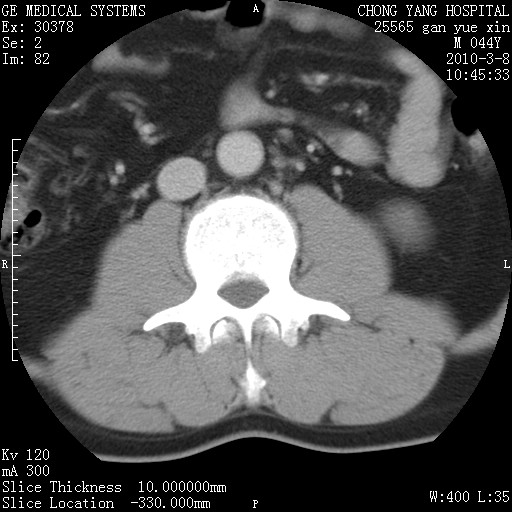

标题: CT24940:主动脉增强,典型病例。 [打印本页]

标题: CT24940:主动脉增强,典型病例。

夹层动脉瘤。

动脉夹层

夹层动脉瘤,典型

主动脉夹层。

动脉夹层的分型:

⒈debakey分型:根据主动脉夹层累及部位,分为三型:ⅰ型:原发破口位于升主动脉或主动脉弓部,夹层累及升主动脉、主动脉弓部、胸主动脉、腹主动脉大部或全部,少数可累及髂动脉。ⅱ型:原发破口位于升主动脉,夹层累及升主动脉,少数可累及部分主动脉弓。ⅲ型:原发破口位于左锁骨下动脉开口远端,根据夹层累及范围又分为ⅲa,ⅲb。ⅲa型:夹层累及胸主动脉。ⅲb型:夹层累及升主动脉、腹主动脉大部或全部。少数可累及髂动脉。

⒉stanford分型:a型:夹层累及升主动脉,无论远端范围如何。b型:夹层累及左锁骨下动脉开口以远的降主动脉。

夹层动脉瘤,少量胸水

夹层动脉瘤;左侧少量胸腔积液。

典型主动脉夹层。